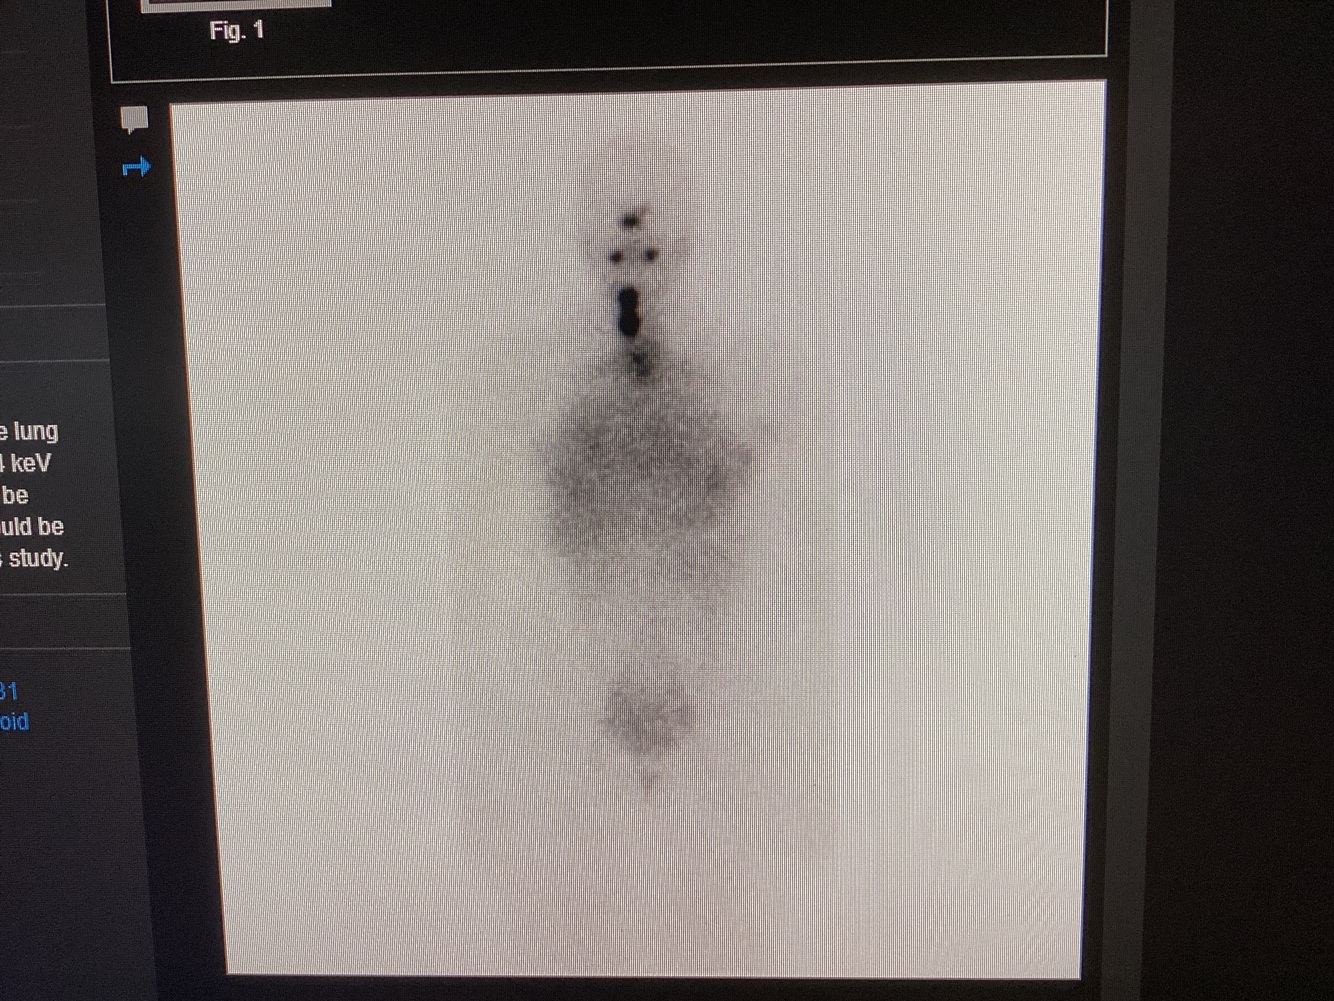

Seven days post-treatment, this scan was obtained. Which collimator was used for this exam? Pinhole, low energy, medium energy or high energy?

High energy; this is a whole body I-131 NaI examination showing residual/recurrent disease in the neck and diffuse lung mets. I-131 has a photopeak of 134 keV, which requires a high energy collimator.